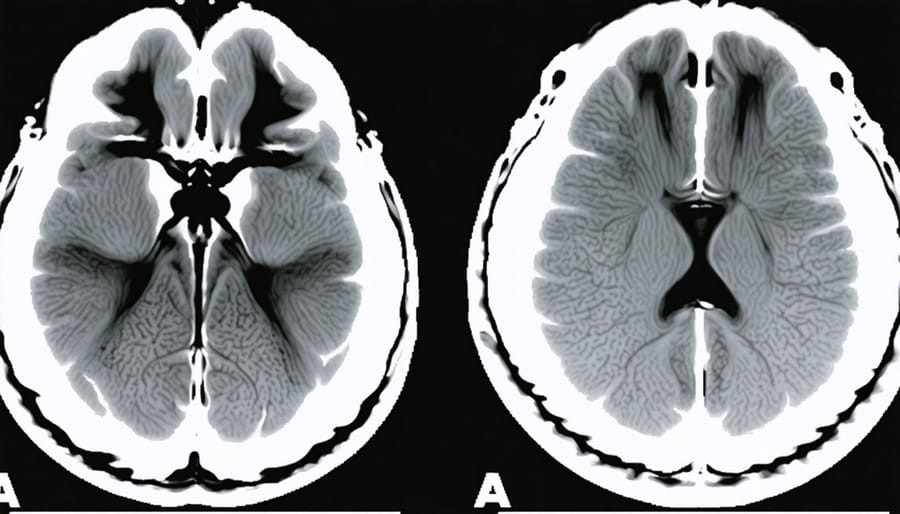

Structural MRI, meanwhile, doesn’t capture the brain in action like its functional cousin. Instead, it’s like taking high-resolution photographs of brain architecture. Researchers use these detailed anatomical maps to investigate whether long-term cannabis use might alter brain structure—questions about hippocampus size or changes in gray matter density. While these structural studies can’t tell us what’s happening moment-to-moment when someone uses THC, they offer crucial insights into potential lasting effects, helping scientists distinguish between temporary changes and more enduring transformations in the brain’s landscape.

Acute vs. Chronic: Different Pictures in the Scanner

Your brain is remarkably adaptable—think of it like a seasoned coffee drinker who eventually needs two cups to feel what one used to provide. When it comes to Delta-9 THC, the difference between someone trying cannabis for the first time and someone who’s used it daily for years shows up dramatically in brain scans, revealing a fascinating story of neural adaptation.

When researchers compare acute users (those experiencing their first or occasional exposures) with chronic users, they’re essentially watching two different movies. In acute users, THC lights up the brain like a fireworks display—the cerebellum buzzes with activity affecting coordination, the limbic system responds intensely to emotional stimuli, and the prefrontal cortex shows significant alterations in decision-making regions. It’s overwhelming because the brain hasn’t learned to compensate yet.

Chronic users tell a different story. Their scans often show what scientists call “blunted responses”—the same dose of THC produces less dramatic changes in blood flow and activity patterns. This isn’t necessarily good news; it’s evidence of tolerance. The brain has downregulated its cannabinoid receptors, similar to turning down the volume on speakers that have been blasting too long. Studies using PET scans have found that heavy, long-term users can have up to 20% fewer CB1 receptors in certain brain regions compared to non-users.

The more concerning findings involve structural changes. Some studies using MRI have reported reduced volume in the hippocampus and amygdala among chronic users—regions critical for memory and emotion. However, other research has failed to replicate these findings, and scientists debate whether observed changes represent actual tissue loss or temporary alterations in how brain cells hold water and nutrients.

What’s particularly intriguing is that not all chronic users show the same patterns. Age of first use matters significantly—adolescent brains appear more vulnerable to lasting changes than adult brains. Frequency and potency also play roles, as does individual genetic variation in how people metabolize THC.

The brain scans essentially reveal a negotiation: acute exposure shows disruption, chronic exposure shows adaptation, but adaptation comes at a cost that may or may not be fully reversible.